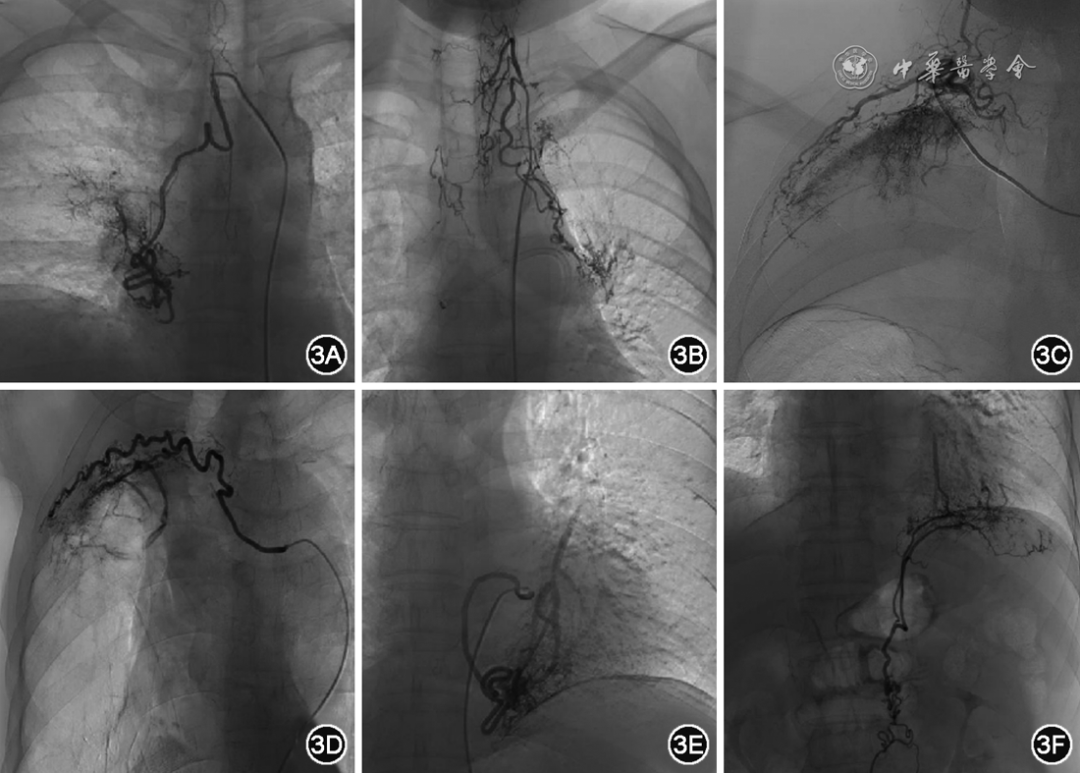

图3  各种异位起源的支气管动脉

注:A为起源于右侧锁骨下动脉支气管动脉,B为异常甲状颈干,C为异常肋颈干动脉,D为异常肋间后动脉,E为异常食管固有动脉,F为异常膈下动脉。